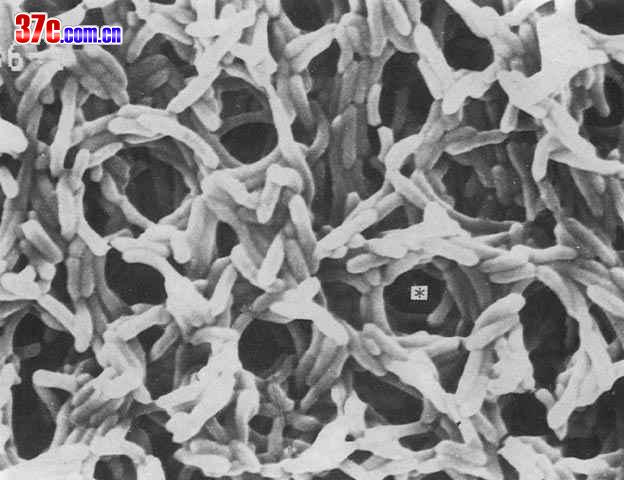

CCTV-2今天中午12:00报道:英国暴发艰难梭菌感染,有近5万人发病。(艰难梭菌的电镜图)

下载

(45.07 KB)

英国:爆发“艰难梭菌”感染

2005-9-6 14:53